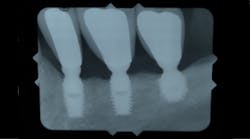

Alternatives to performing these additional augmentation procedures in cases where patients have atrophic posterior regions have come in the form of shortened implants (figures 1 and 1a). Short implants have been defined in the literature as implant lengths that are less than 10 mm. (6) Although the use of short implants seems to be an obvious alternative in cases where conventional implants are not an option without additional procedures, the question is: Do short implants have the same survival rates as conventional-length implants? The answer has been mixed in the historical literature. (7)

Figure 1: Short implants placed more than 20 years ago to avoid inferior alveolar nerve

Figure 1a: Short implant placed more than 10 years ago to avoid maxillary sinus